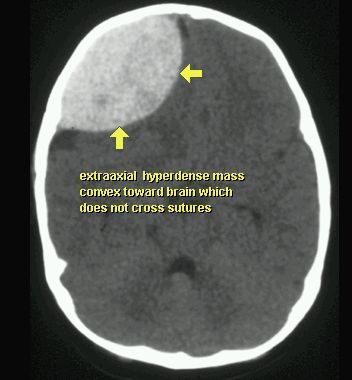

KRWIAK NADTWARDÓWKOWY

TK